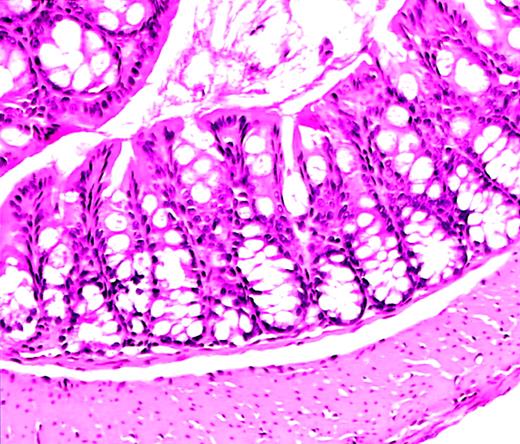

Normal colon histology in C57−WAS− mouse after transplantation.

Hematoxylin and eosin–stained section from the colon of a C57/BL6J WAS-null mouse (age 10 weeks, H hepaticuspositive) that became acutely ill and was killed 10 days after lethal irradiation and bone marrow transplantation. A severe hemorrhagic cystitis was found at necropsy. Colon histology shows rare acute and chronic inflammatory cells, but is essentially normal. Magnification, × 50.

The utility of the C57/BL6J mouse strain for study of HSCT is well established.7-9 We crossed 129/SvEv WAS-null mice (129−WAS−) for 2 to 4 generations onto the C57/BL6J background. Necropsy studies of C57/BL6J WAS− (C57−WAS−) males revealed normal colons without the inflammatory infiltrates and crypt abscesses previously reported on the 129/SvEv background.6A slightly increased number of mononuclear cells in the lamina propria was found in WAS-null animals compared with wild-type (WT) littermates, an abnormality slightly exacerbated by irradiation (Figure1). Necropsy studies of 129−WAS− males revealed only acute and chronic inflammatory cells in the colonic lamina propria in 1 of 3 animals.